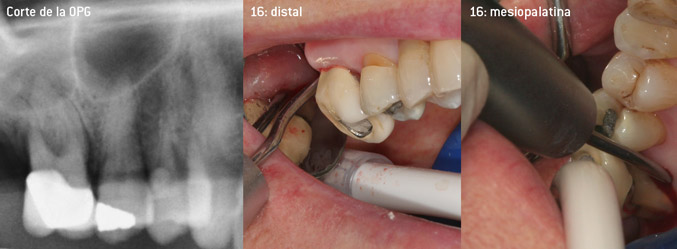

Como precursores del desarrollo de la nueva punta diamantada 3AP para eliminadores de sarro neumáticos, los dos odontólogos constataron que era necesario limitar el uso de las puntas diamantadas que se estaban comercializando hasta la fecha, sobre todo durante los tratamientos de furcaciones o en bolsas interradiculares estrechas. Además, esto debe llevarse a la práctica independientemente de si se trata de un procedimiento no quirúrgico (figura 2) o de un procedimiento quirúrgico (figura 3).

Fotos (figuras 2 -4): © Dr. Christian Graetz)

El objetivo principal consistía en desarrollar una punta de uso universal para no tener que perder tiempo al cambiar de punta de un tratamiento a otro. No obstante, también se pretendía que el uso de las nuevas puntas fuera más sencillo, tanto en bolsas periodontales estrechas desde el lado distal como en la entrada de furcaciones distales en los molares superiores, de manera que el tratamiento con instrumentos resultara más eficaz. Esto se consiguió aumentando el diámetro del arco del instrumento (figura 1), lo que representa una enorme ventaja durante el desbridamiento cerrado, sobre todo en el caso de piezas dentales con pérdida de adherencia avanzada y lesiones de furcación (figura 4).